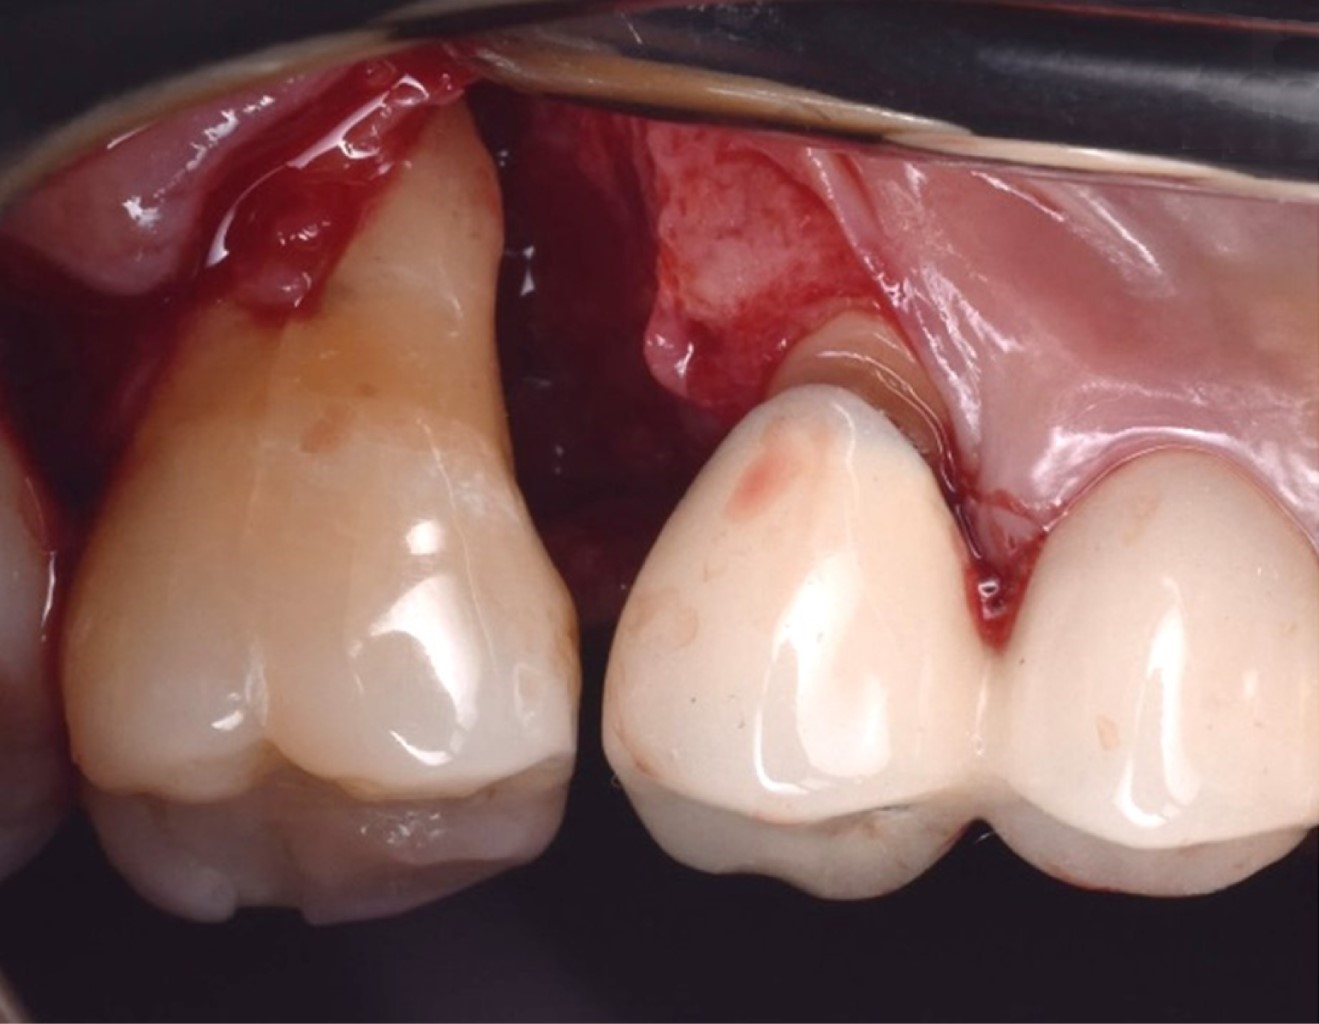

Las proteínas derivadas del esmalte (Emdogain®) se obtienen por medio de la odontogénesis en el periodo de yema de la dentadura porcina; la proteína principal es la amelogenina que presenta una biocompatibilidad con las proteínas del esmalte humano. Los cultivos in vitro han demostrado que Emdogain® al ser agregado a los fibroblastos causa una mejora en la producción de proteínas y colágeno, mineralización y proporciona condiciones favorables a la matriz, proliferación celular, migración, diferenciación y síntesis (Figuras 1, 2, 3, 4, 5 y 6). La capacidad osteogénica se relaciona de manera directa con las proteínas que contiene y esto produce una capacidad osteoinductiva y puede contener factor de crecimiento transformante beta y proteína morfogénica ósea (BMP, por sus siglas en inglés) aunque en menor cantidad.10

Se presenta, en la Especialidad en Periodoncia de la Universidad Autónoma de Baja California (UABC) campus Mexicali, un paciente femenino de 60 años, ASA I, sin antecedentes patológicos, cuyo motivo de consulta es "tengo una bolsa periodontal desde los ocho años". Se realizó una evaluación extraoral en la que se detectó hipertrofia bilateral del músculo masetero, de manera intraoral se observó un fenotipo delgado, presencia de restauraciones desajustadas, desgaste por bruxismo en bordes incisales y cúspides. En el análisis clínico-radiográfico se obtuvo una profundidad de sondaje de 12 mm, efecto intraóseo de una pared según la clasificación de Goldman & Cohen (Figura 7) por vestibular del segundo molar superior derecho, movilidad grado II, con presencia de sangrado, sin sensibilidad. Radiográficamente se observó una zona radiolúcida adyacente a la raíz mesial del segundo molar superior derecho sin presencia de lesión periapical (Figura 8) y, por lo tanto, se estableció el diagnóstico según la "Clasificación de Condiciones y Enfermedades Periodontales y Periimplantarias 2017" como: salud gingival y periodontal en un periodonto reducido, paciente no periodontal, asociado a un trauma oclusal primario;11 y como factor de riesgo se tiene el antecedente de la pérdida prematura del primer molar superior derecho y la mesialización del segundo molar superior derecho.

Figura 1

Figura 2

Figura 3

Figura 4

Figura 5

Figura 6